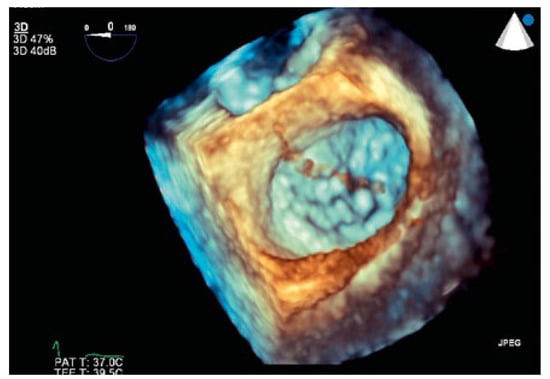

Thrombus in Transit

Case presentation